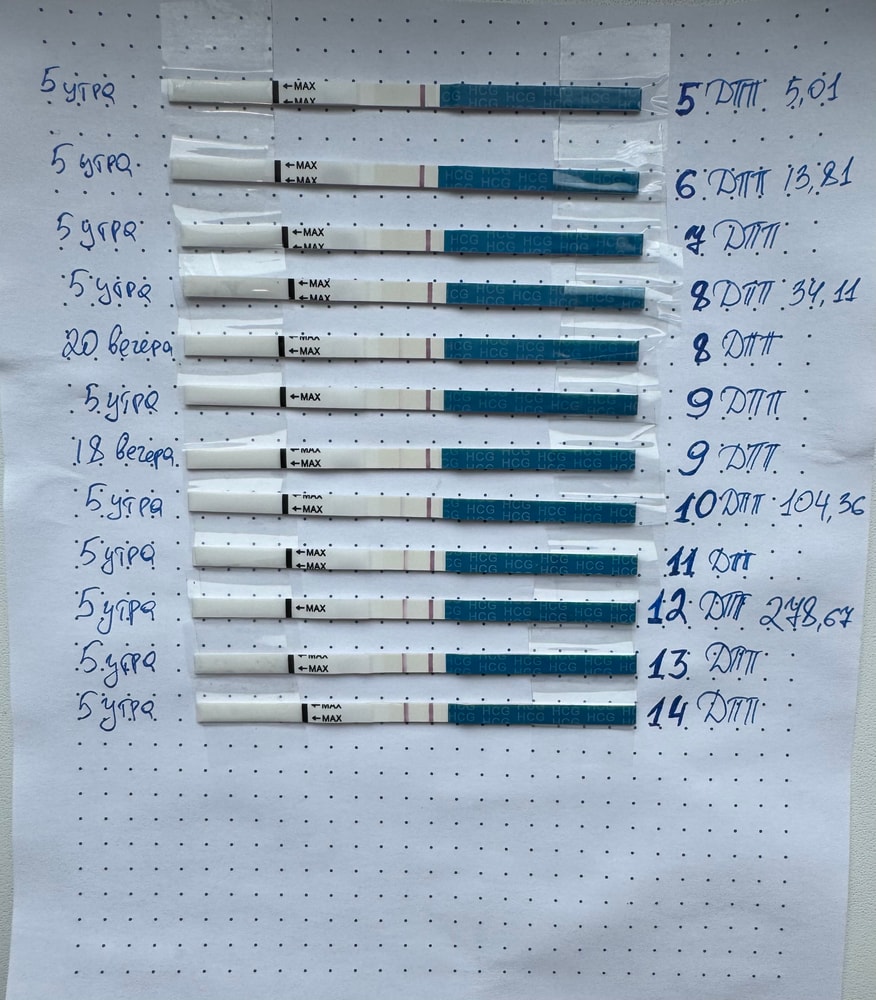

Далее переживания за низкий хгч и полупрозрачные тесты, весь форум перерыла. Видимо поздняя имплантация существует.